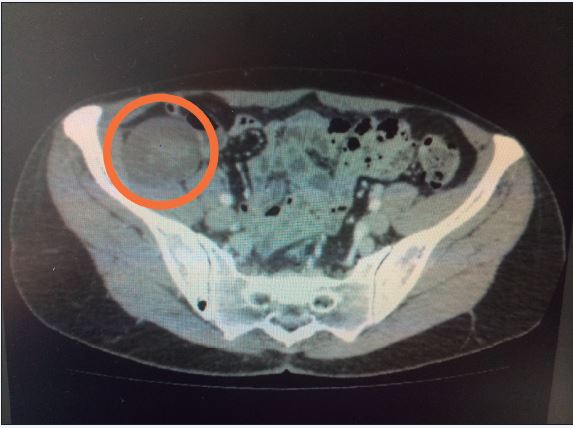

Mujer de 54 años con antecedente de linfoma folicular de bajo grado diagnosticado 1 año antes. En este contexto, presenta una tumoración sólida en fosa iliaca derecha, con crecimiento en los últimos 3 meses y una biopsia por punción-aspiración con aguja fina (PAAF) previa que no fue concluyente para diagnóstico, sin poder descartar por técnicas de imagen, tomografía axial computerizada (TAC) y resonancia nuclear magnética (RNM). que la lesión fuera de estirpe maligna ( Fig. 1 ).